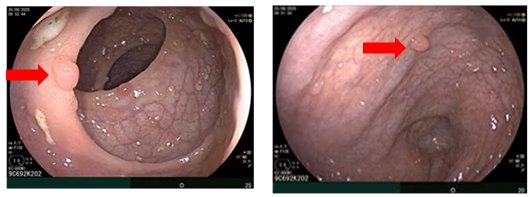

Hình 3

. Hình ảnh các polyp rải rác ở đại tràng (mũi tên đỏ)

Hình 5

. Hình ảnh khối buồng trứng phải kích thước ~108mm (mũi tên màu cam), khối buồng trứng trái kích thước ~58mm (mũi tên màu xanh lục) trên phim chụp cắt lớp vi tính.